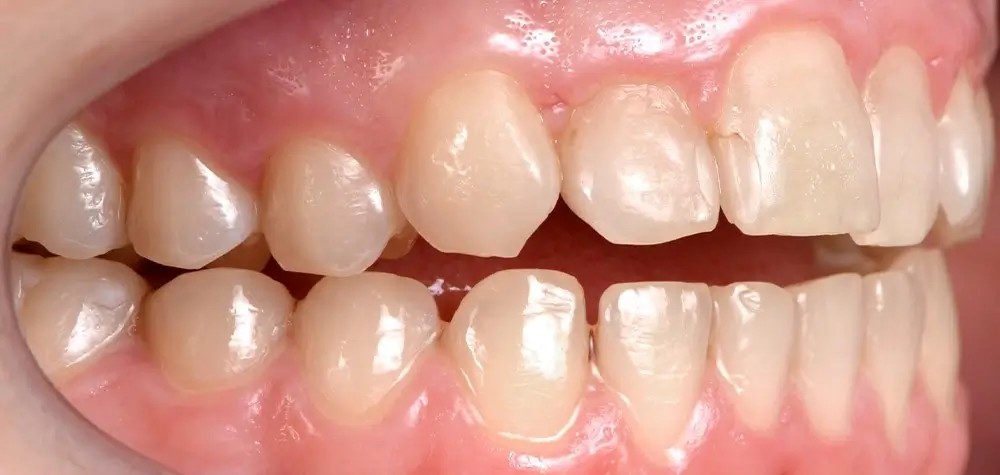

Открытый прикус - Кейс 2

Эффективность устранения дефекта прикуса посредством элайнеров FlexiLigner.

Результаты лечения